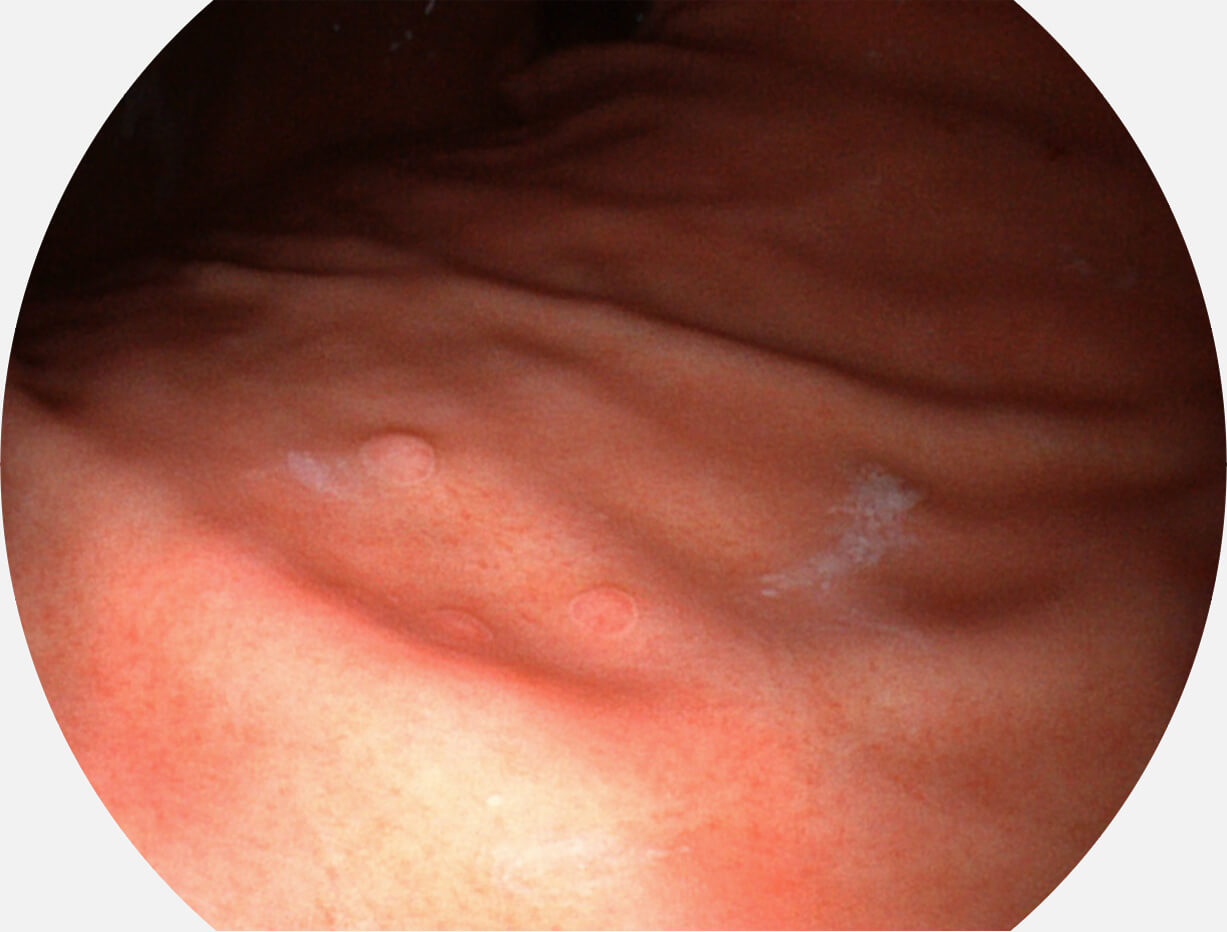

Versatile Intelligent Staining Technology, VIST

强调浅层黏膜结构的同时,保证照明亮度和提升浅层微血管与中层血管颜色对比度,病变边界更清晰。

白光图像

VIST图像